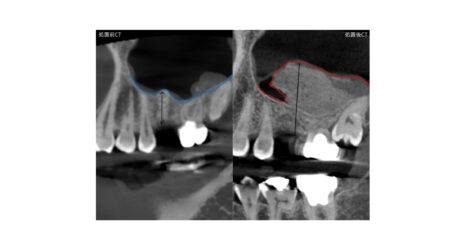

この方は元々根の治療をされた所が悪くなり、根っこの先の膿の袋が大きくなり骨を壊して骨が足りず一度GBRという骨造成をした後に追加でサイナスリフトとい処置を行いました。

上あごの骨は元々薄く骨が溶けてしまうと更に薄くなってしまい、インプラントを支える骨の高さが無くなってしまいます。

骨の高さが無いとインプラントは出来ない為、先に骨を作る治療が必要になります。